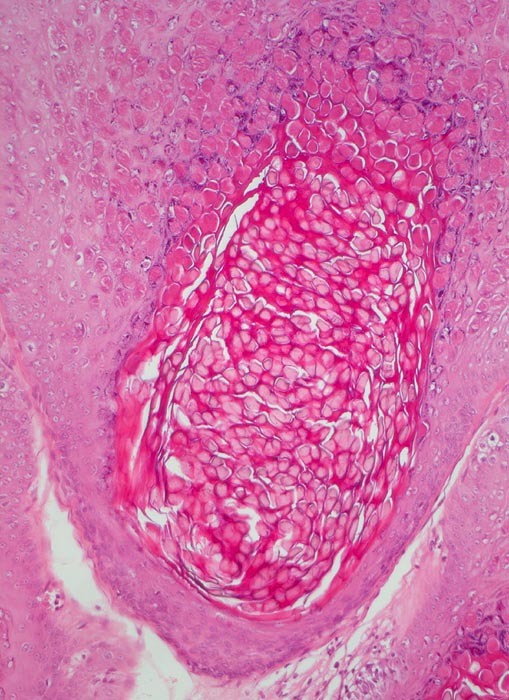

AP/ Molluscum contagiosum

Molluscum contagiosum

Dellwarzen imponieren als schmerzlose oder juckende fleischfarbene Knötchen mit einem zentralen Nabel (Delle). Sie treten einzeln oder multipel auf (meist nicht mehr als 20). Der Durchmesser beträgt meist 2-6mm, selten bis zu 3cm. Eine bakterielle Superinfektion der Läsionen mit Pustelbildung und Erythem ist möglich. Die Epidermis ist akanthotisch und kann bis zu 6 mal dicker sein als normal. Die Basalzellen sind etwas vergrössert und hochprismatischer. Das Molluscum Körperchen ist das Ergebnis einer viral induzierten Zytoplasmareaktion. Die multiplen intrazytoplasmatischen Einschlüsse enthalten Viruspartikel. Die Viruspartikel werden grösser in Richtung Granularzellschicht und verdrängen den Zellkern zur Seite. Die Dermis unterhalb des infizierten Molluscum Körperchens ist abgesehen von gelegentlich nachweisbaren Entzündungszellen unauffällig.

• Akanthose und Papillomatose der Epidermis.

• Kugelige eosinophile intrazytoplasmatische Einschlüsse in Zellen von Stratum granulosum und Stratum corneum.